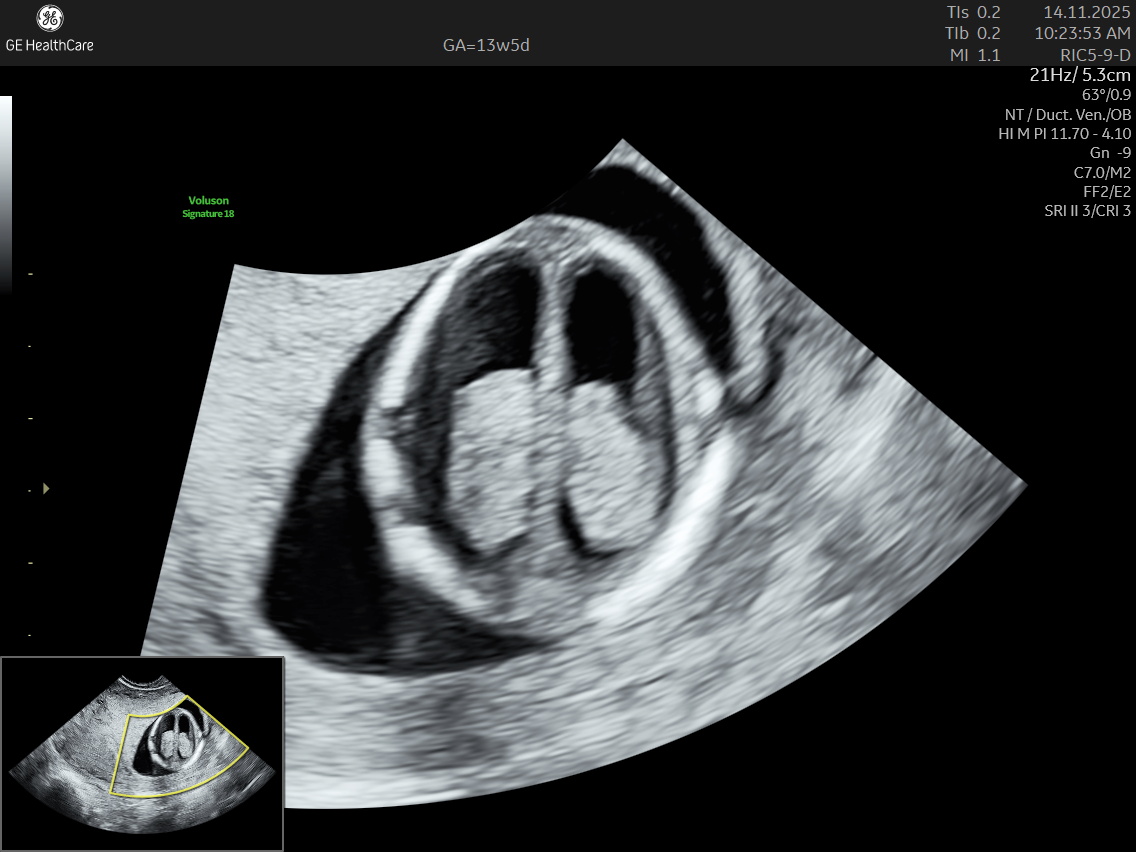

- Congenital heart defects, which are among the most common physical birth defects, including septal defects and tetralogy of Fallot.

Although the NT scan is mainly a screening tool and not diagnostic on its own, it can identify about 50% of major fetal abnormalities when combined with other assessments like blood tests and detailed ultrasound. The scan also helps to screen some basic anatomical structures during the first trimester, especially the fetal heart anatomy, brain, face, spine, stomach, abdominal wall, kidneys, bladder, and extremities to varying degrees depending on gestational age and maternal factors.